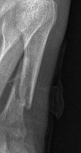

Ameliyat olmadan durumuna göre iyileşir onuda doktorun/doktorların karar verir en iyi şekilde. 2005 yılında merdivenden düştüm, düşerken sol ayağım iki basamak arasına girmişti. Topuğumdan diz altına kadar bütün kemikler tabiri caizse tuz gibi olmuş. Doktorlar çok yoğun kırık olmasından dolayı ameliyat etmediler hatta alçıya bile almadılar. Sadece bandaj ile sabit dursun diye sardılar. 2. ayın sonunda üzerine basmaya , sekerekte olsa yürümeye başladım. 6 ay içinde sanki hiç kırılmamış seviyesine gelmişti.Hepinize teşekkür ederim arkadaşlar. Sürüş arkadaşlarımdan birisi sağolsun trafik jandarma, polis vs ne varsa çağırıp tutanak tutturmuş benim haberim yok çünkü kendimde değildim. Dün akşam arkadaşlarımdan biri garmin edge, bisiklet çantası ve alet çantasını getirdi ve yarın sabahta kısmet olursa diğer arkadaşım bisikleti emanet ettiği marangozdan alıp evime getirecek. Önümüzdeki bir iki ay boyunca sanırım yatarak geçireceğim. Cuma günü babamın yardımı ile hastaneye gidip rapor vereceğim ve jandarma gelecek ifademi almaya. Hem maddi hem manavi olarak büyük bir kayıba yol açtı bu kaza. Bu işin peşini bırakmayacağım. Babamın anlattığına göre bana söven kadın hastanedeyken aramış ve çok özür dilemiş. Daha önce hiç kırık geçirmedim, ameliyat olmadan kırık gerçekten iyileşebiliyor mu? Valide hanım sağolsun çok yardımcı oluyor kemik ilik suyu vs olsun besliyor beni. Bugünde sipariş verdiğim vitaminler elime ulaştı.